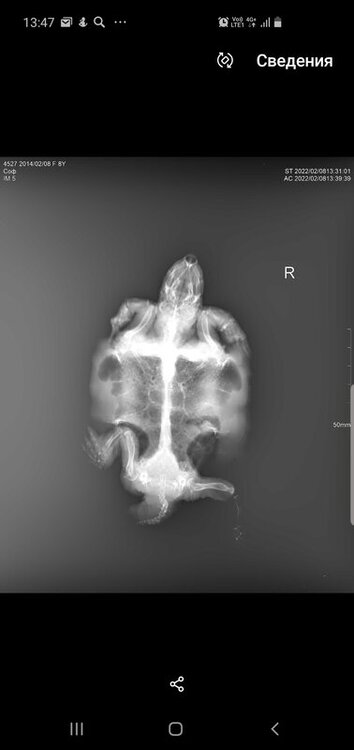

Консультанты moth Ваше имя: Мария Локация: Москва Опубликовано: 8 февраля 2022 Консультанты Опубликовано: 8 февраля 2022 @Зюлиф нет, к сожалению я в снимках могу только что-то простое увидеть - газы или яйца или инородное тело. У Вас всё сложно из-за деформации панциря.

Зюлиф Ваше имя: Софа Локация: Набережные Челны Опубликовано: 8 февраля 2022 Автор Опубликовано: 8 февраля 2022 1 час назад, moth сказал: @Зюлиф нет, к сожалению я в снимках могу только что-то простое увидеть - газы или яйца или инородное тело. У Вас всё сложно из-за деформации панциря. Все же прикреплю пару фото.И вопрос:сегодня доставили уф лампу simple zoi bulk UVB10.0 13W,на каком расстоянии вешать ее от островка,подскажите, пожалуйста

Консультанты moth Ваше имя: Мария Локация: Москва Опубликовано: 8 февраля 2022 Консультанты Опубликовано: 8 февраля 2022 @Зюлиф я тут вижу только, что лёгкие мутные, но это могут и органы перекрывать. Я понимаю, что ожидание ответа может быть некомфортным, но это в реальности быстрее очных приёмов тех же самых, на них может быть запись и неделю-две.

Консультанты moth Ваше имя: Мария Локация: Москва Опубликовано: 10 февраля 2022 Консультанты Опубликовано: 10 февраля 2022 @Зюлиф как нету, в 2.35 она Вам написала, посмотрите телеграмм По поводу рентгена: - Объем легких незначительно снижен - Есть признаки скопления экссудата (жидкости), что может говорить как раз о пневмонии. - Плотность костных структур снижена, неравномерная. а дальше как раз про лечение и антибиотик